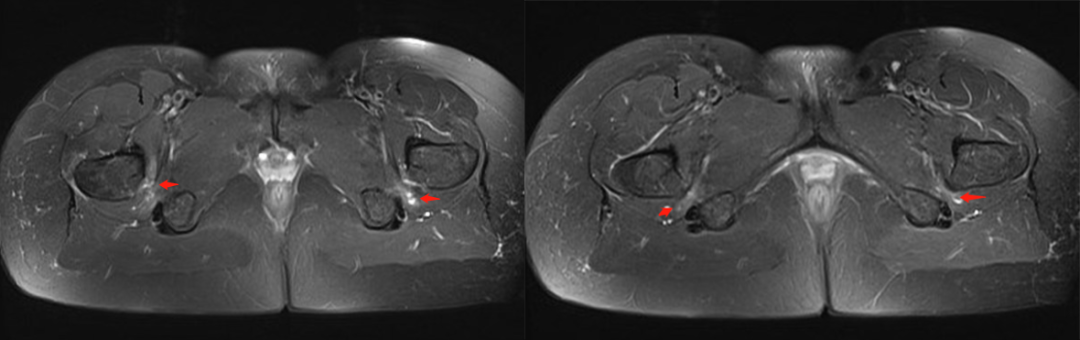

1. 坐骨股骨间隙变窄,坐骨股骨间隙是坐骨结节外侧骨皮质到股骨小转子内侧骨皮质的最窄距离,正常坐骨股骨间隙正常人群组为 23±8 mm,若间隙﹤15 mm 可视为狭窄。

2. 股方肌间隙变窄,股方肌间隙是股方肌通过的最窄间隙,其后内侧边界是腘绳肌肌腱止点的外上表面,前外侧边界是髂腰肌肌腱或股骨小转子的后内侧表面,测量这两个边界之间的最短距离。正常股方肌间隙人群组为 12±4 mm,若间隙﹤8 mm 可视为狭窄。

3. 股方肌以位于坐骨股骨间隙最狭窄处的肌腹为中心出现水肿信号或挤压变形。

测量方式:坐骨-股骨间隙测量 两侧相比右侧坐骨-股骨间隙缩小

股方肌位于狭窄处出现水肿